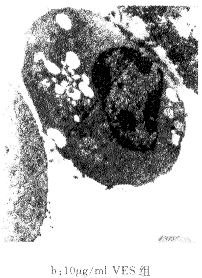

二、电镜观察SGC-7901细胞的凋亡

VES处理SGC-7901细胞48小时后电镜观察见到典型的细胞凋亡特征(图2)

图2 VES处理SGC-7901细胞的形态观察

从图2中可见,对照组没有发生凋亡的细胞有绒毛,线粒体细胞器正常,而在VES处理后的SGC-7901细胞可见染色质浓集成块状,绒毛消失,染色质固缩边集在核膜四周呈新月状小体(图2-b),并可见凋亡小体(图2-C)。